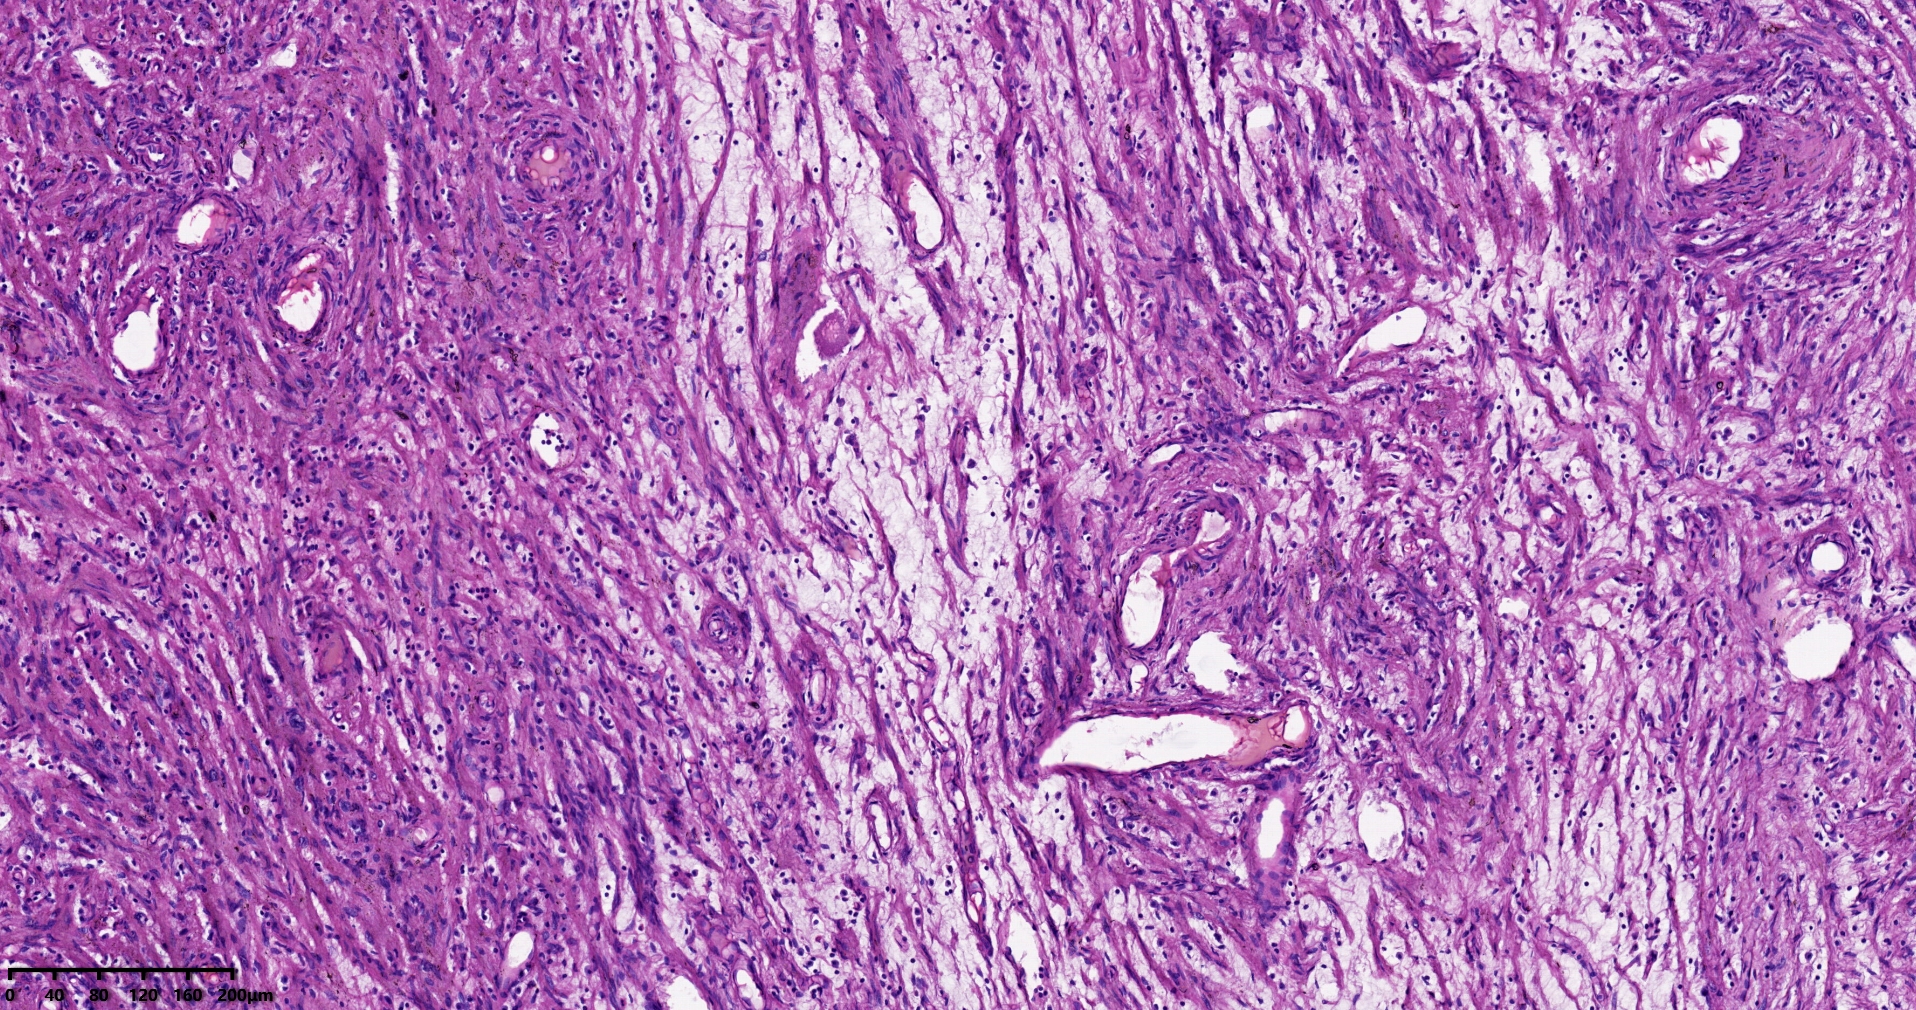

结肠肝曲息肉状肿物,平滑肌瘤?胃肠道间质瘤?炎性纤维性息肉?

大体所见

灰红色椭圆形息肉一个,直径2.5cm,蒂长0.5cm,切面灰白灰红色,质中。

考虑间质瘤?

就HE形态而言,间质瘤的可能性要大一些,建议做免疫组化协助鉴别。